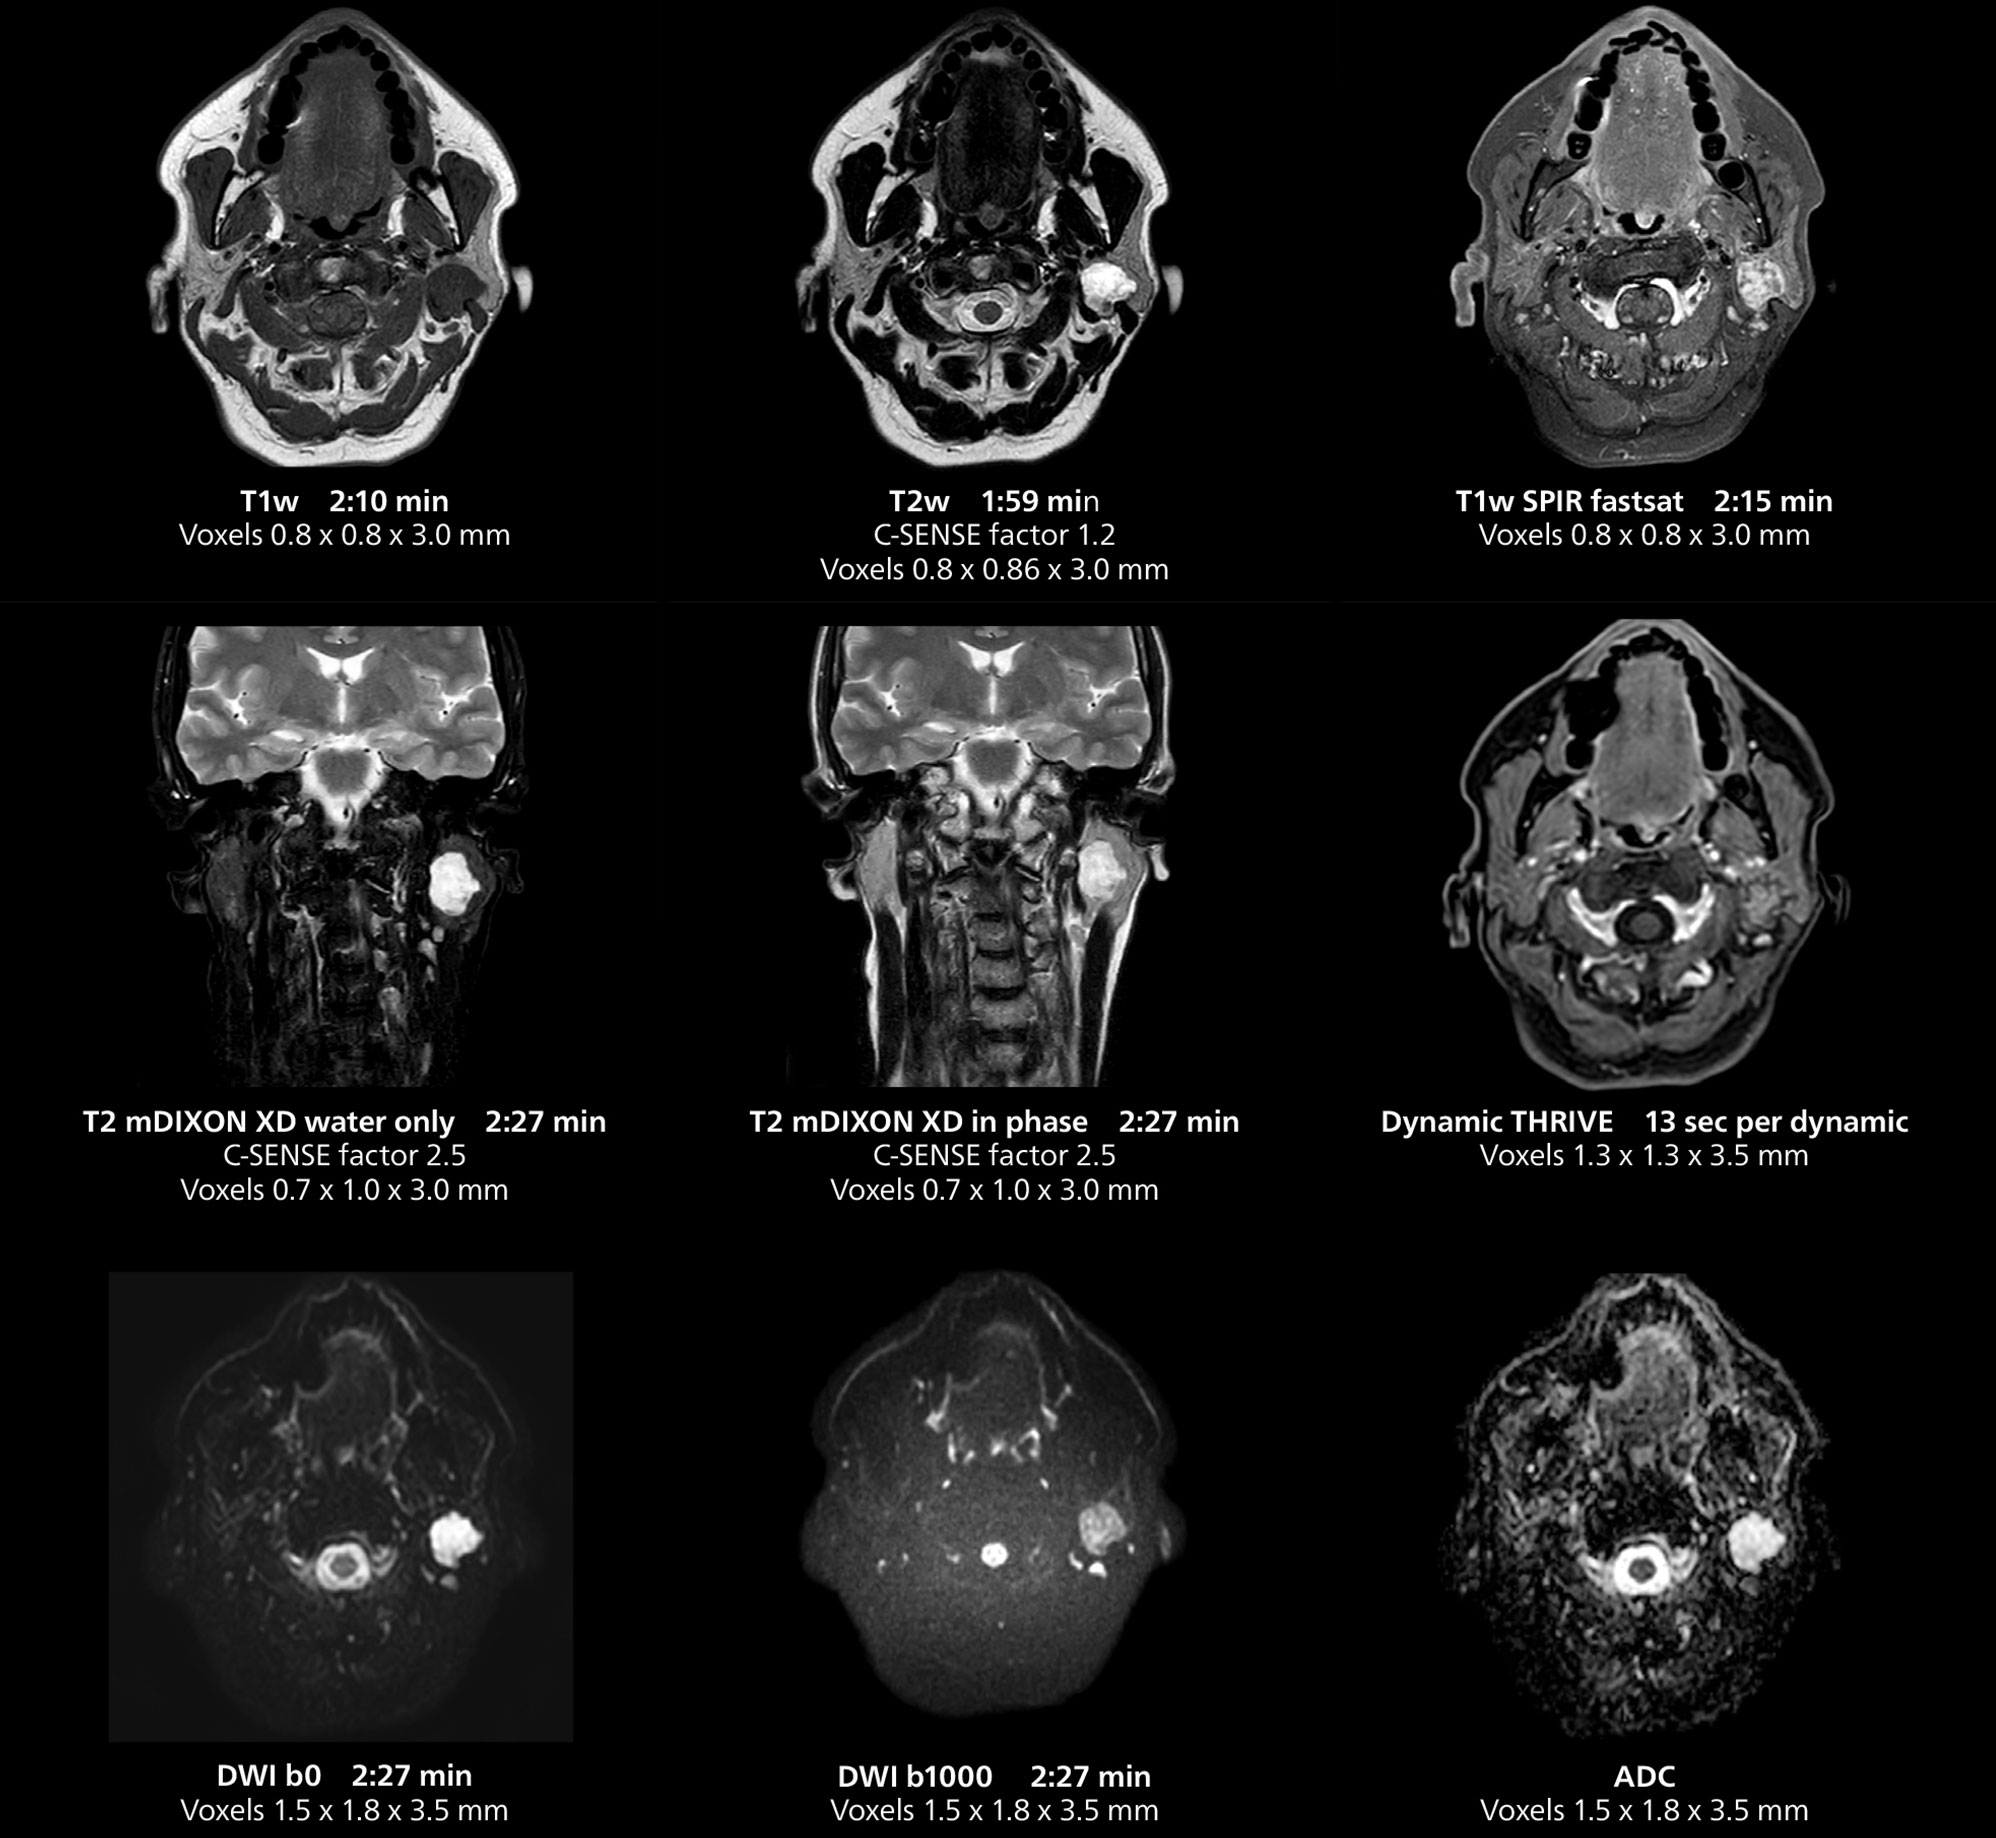

This MRI case illustrates imaging of salivary gland abnormalities with different sequences. Compressed SENSE allows to accelerate scanning while maintaining high quality. With mDIXON XD, different contrast types can be obtained from scanning one sequence.